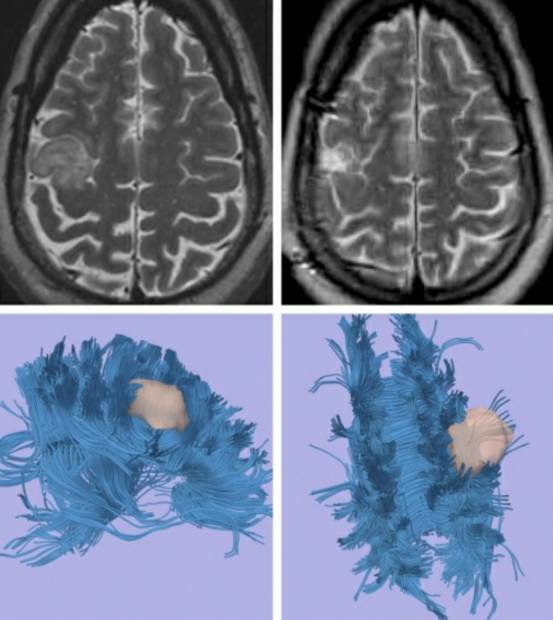

病例3:男性,45岁,表现为左侧局灶运动性癫痫发作。

图9. 影像学提示右侧中央小叶胶质瘤(左上图)。病变位于运动功能区,考虑可能无法手术切除。然而,DTI成像(下图)提示功能区纤维束受推挤移位,提高了笔者安全切除肿瘤的信心。使用脑皮层和皮层下定位实现肿瘤全切,术后无遗留任何神经功能障碍(右上图)。